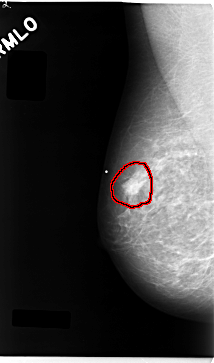

C_0043_1.RIGHT_MLO

RIGHT_MLO LINES 4712 PIXELS_PER_LINE 2776 BITS_PER_PIXEL 12 RESOLUTION 50 OVERLAY

FILE: C_0043_1.RIGHT_MLO.OVERLAY

TOTAL_ABNORMALITIES 1

ABNORMALITY 1

LESION_TYPE MASS SHAPE IRREGULAR MARGINS MICROLOBULATED

ASSESSMENT 5

SUBTLETY 5

PATHOLOGY MALIGNANT

TOTAL_OUTLINES 1

BOUNDARY